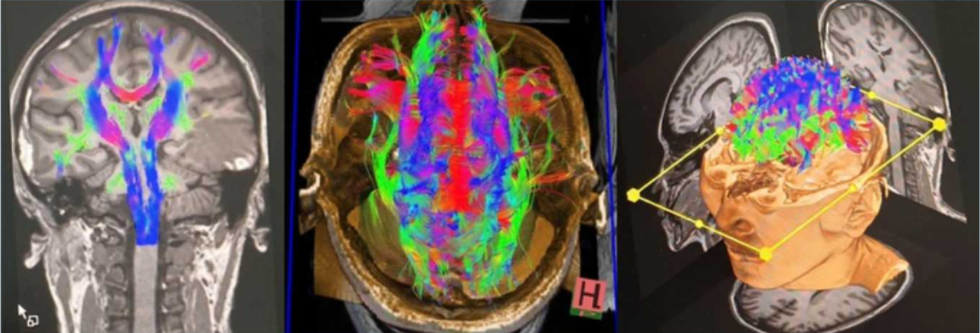

西门子3.0T磁共振不仅能“看”到神经系统的形态结构,更能“看”懂其功能状态。它支持多种先进的功能成像序列,如弥散张量成像(DTI)和功能磁共振成像(fMRI),这使其被广泛认为是神经科学研究和临床诊断的“金标准”。

脑血管疾病的“侦察兵”:对于急性脑梗死,3.0T磁共振的弥散加权成像(DWI)序列极为敏感,能够在数分钟内发现缺血病灶。对于脑动脉瘤、血管畸形等“不定时炸弹”,3.0T的高质量血管成像(MRA)技术无需使用对比剂,即可清晰显示血管的形态和走向,为临床决策提供可靠依据。

脑肿瘤的“定位仪”:3.0T磁共振的高分辨率能够清晰显示肿瘤的大小、位置、边界及其与周围重要结构(如神经、血管)的关系。结合增强扫描和波谱分析等技术,还能帮助医生判断肿瘤的良恶性,为制定精准的手术方案或放化疗计划提供关键信息。